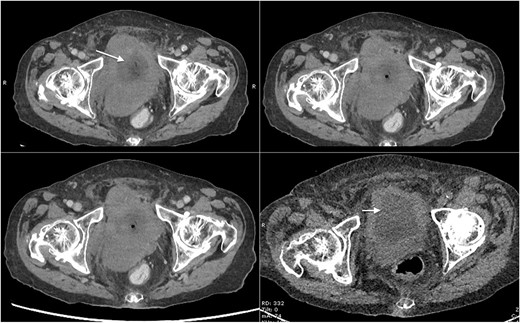

Based on her clinical presentation, an urgent magnetic resonance imaging (MRI) of whole spine scan was performed, which revealed severe bilateral hydroureteronephrosis. Scout imaging showed irregular bladder wall thickening and moderate canal stenosis at L4/L5 with no evidence of cauda equina syndrome. Computed tomography (CT) with contrast medium was then performed for the abdomen and pelvis together with KUB. It revealed moderate to severe bilateral hydroureteronephrosis down to the urinary bladder with a lesion resembling like a possible posterior wall urinary bladder tumour (Fig. 1). There was no faecal impaction with mild ascites and no compression of the posterior wall tumour on the bowel. No evidence of perforation was present.

Axial CT scan of abdomen and pelvis with contrast showing mass lesion in the bladder (marked with arrows).